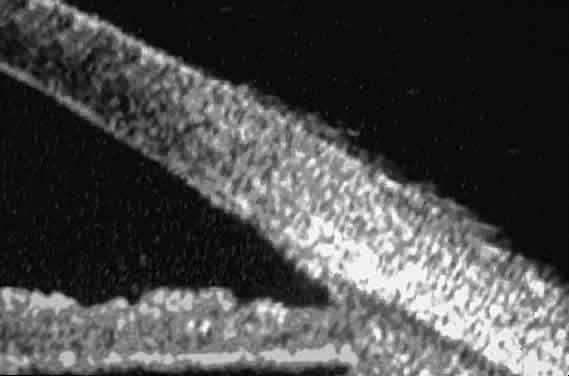

The role of UBM in the preoperative assessment of eyes with cataract is as yet unknown. In certain eyes, however, UBM may reveal features or abnormalities that could alter the ophthalmologist's surgical approach. Postoperatively, UBM can show the size and location of an intraocular lens (IOL) and the positioning of the haptics. A posterior chamber IOL appears on UBM as a highly reflective plate (corresponding to the lens optic) in the retropupillary plane with reverberation artifacts behind it (Fig. 17A). In contrast, an anterior chamber IOL appears on UBM as a sonoreflective plate located anterior to the pupillary plane (see Fig. 17B). In most eyes with a posterior chamber IOL, UBM can show whether the haptics are in the capsular bag (Fig. 18A), in the ciliary sulcus (see Fig. 18B), or in some other anatomic location12 (e.g., resting on the peripheral iris or secured with sutures to the sclera). The haptics are easier to locate if they are made of polymethyl-methacrylate than if they are made of proline because the former has a stronger reflectance.

Fig. 17. Composite UBM images of intraocular lenses. A. Posterior chamber IOL. B. Anterior chamber IOL.

Fig. 18 . Localization of posterior chamber IOL haptics by UBM. A. Haptic in capsular bag (arrow). B. Haptic (bright object just behind peripheral iris) in iridociliary sulcus.